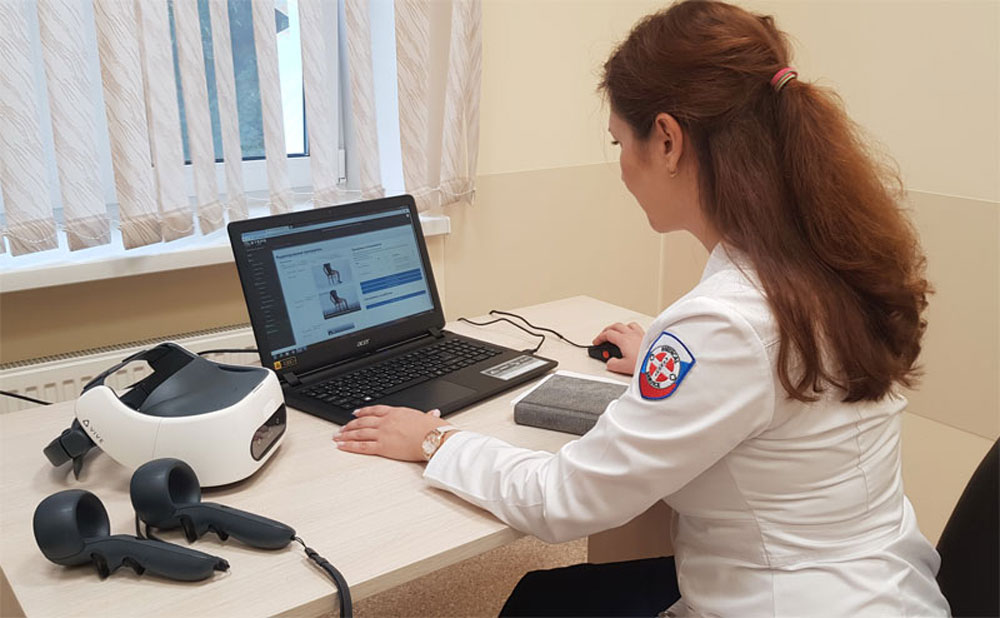

Пироговский Центр и стартап «Виртуальная реабилитация» представили отечественную цифровую платформу для дистанционной реабилитации с применением технологий виртуальной реальности и биологической обратной связи VRmedSoft на VII ежегодной конференции «Цифровая индустрия промышленной России» (ЦИПР-2022) в Нижнем Новгороде.

Компания «Степс Спорт» под научным руководством Генерального директора Пироговского Центра, члена-корреспондента РАН, профессора Олега Карпова стала резидентом инновационного научно-технологического центра «Сириус» с проектом по созданию «Платформы цифровой реабилитации взрослых и детей».

Пироговский Центр открыл свободный доступ к онлайн-платформе реабилитации для медучреждений и органов соцзащиты.

Решение «Степс Реабил» вошло в проект «Лучшие практики борьбы с пандемией».

Внедрены новые возможности телемедицины, в том числе готовые цифровые решения для двигательной, речевой и психологической реабилитации на домашнем этапе лечения, что обеспечивает наибольшую эффективность и непрерывность процесса восстановления наших пациентов